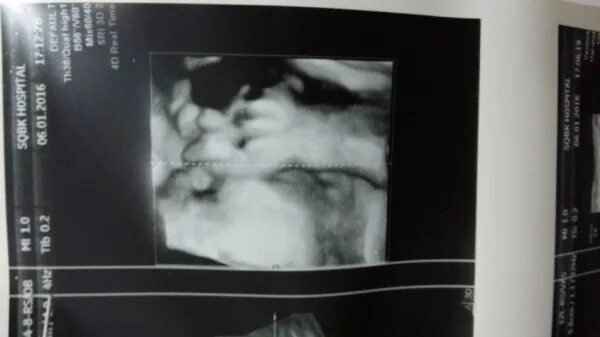

39 недель нет предвестников